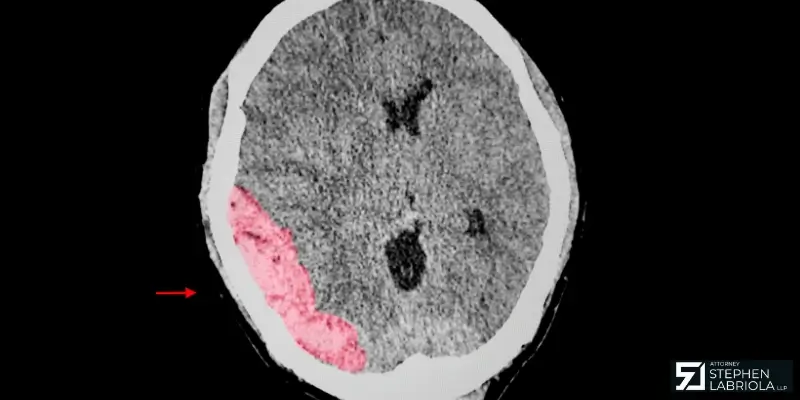

A traumatic brain injury in a legal claim is proven using medical records, brain scans, and testimony from doctors. In some cases, specialists can explain how the injury affects your memory, speech, or behavior. It’s also important to show how the injury happened and how it changed your life. The more clearly the impact is documented, the stronger the claim.